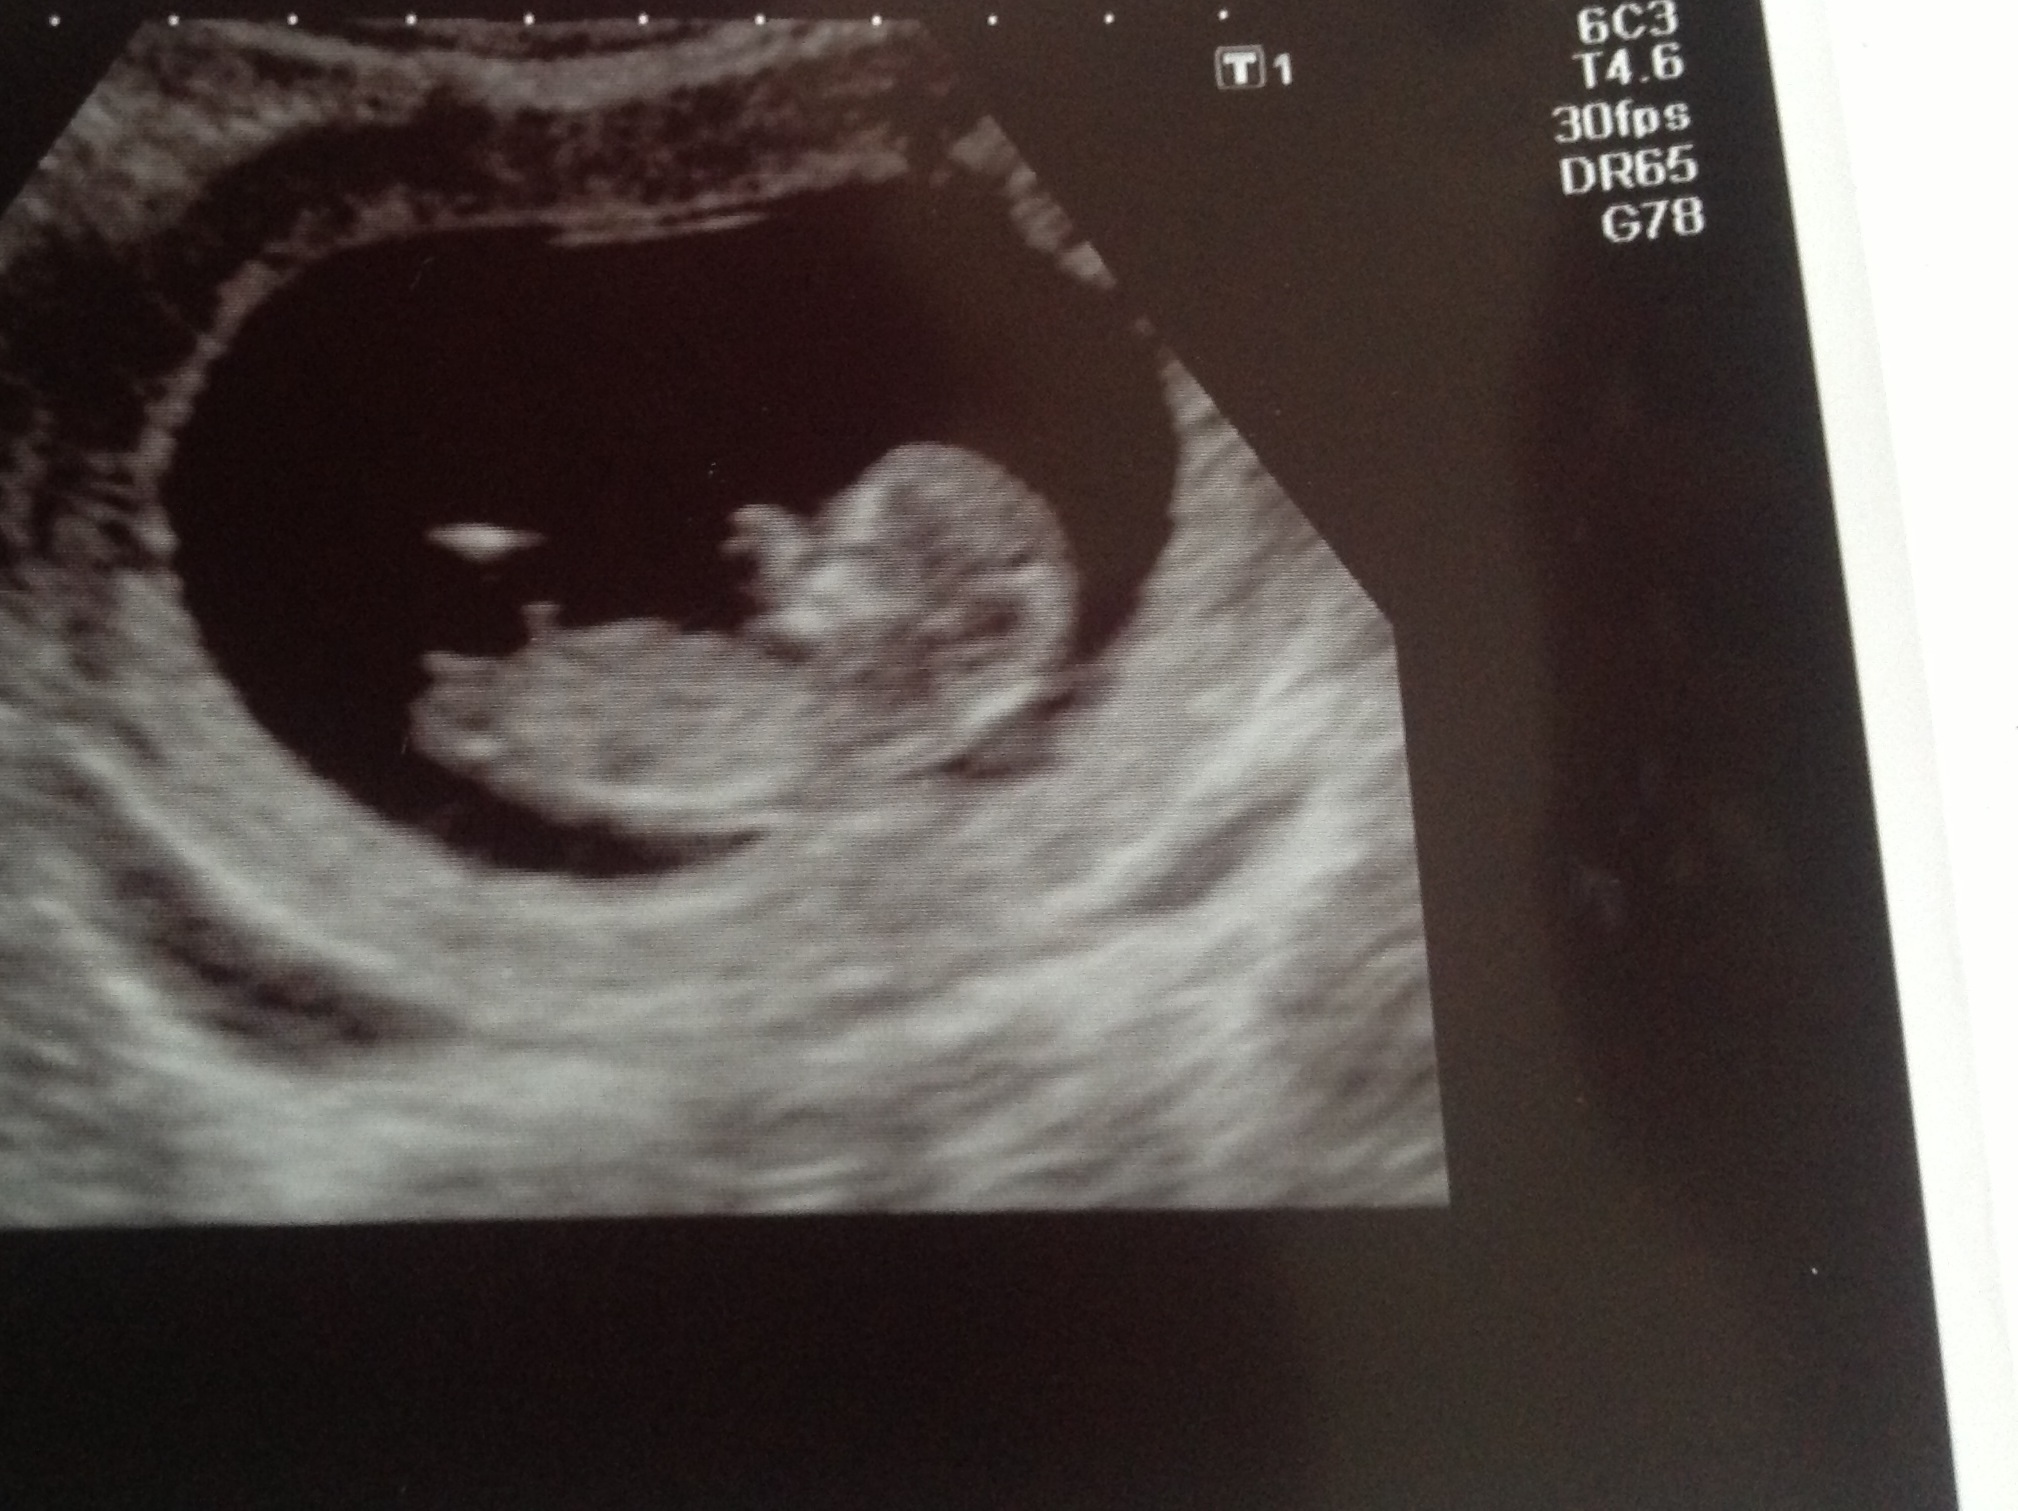

What do you think? The shots are of the same baby - ignore twin A written at the bottom! Not sure what that is about but there is only one on there!:)Attachment 11906

Slightly different shot

What was the gestation? slight boy lean for me

I'm going to have to guess boy too. Looking at the spin and nub there appears to be a slight angle which could increase as the weeks move on (not sure how many weeks you are). Beautiful baby :)

I am 12 weeks one day so still plenty of time to angle up. I really hope it doesn't though. I am trying to keep an open mind as I think it could go either way and don't want to get too invested in either result.

Yah, based on the first pic. To me there isn't a nub in the second pic I don't think. That's funny the tech knew about nub theory, maybe she's good at guessing! I only say boy because of the slight lean and being 12 weeks it still rises apparently (heard several ladies say that 13.5 weeks is the best because things don't rise anymore after that). I feel like most girl nubs are super flat and very straight.. only reason why I'm slightly leaning boy. I wouldn't bet my children on it or anything though ;)

The tech said the nub was flattish but the spine was a bit curved so that the angle is still good for a girl. I thought that if the spine wasn't flat it couldn't be used for nub guessing? Is that right?

As for the spine, I thought the idea was to use the angle of the bottom of the spine as your guide for comparing the angle of the nub?